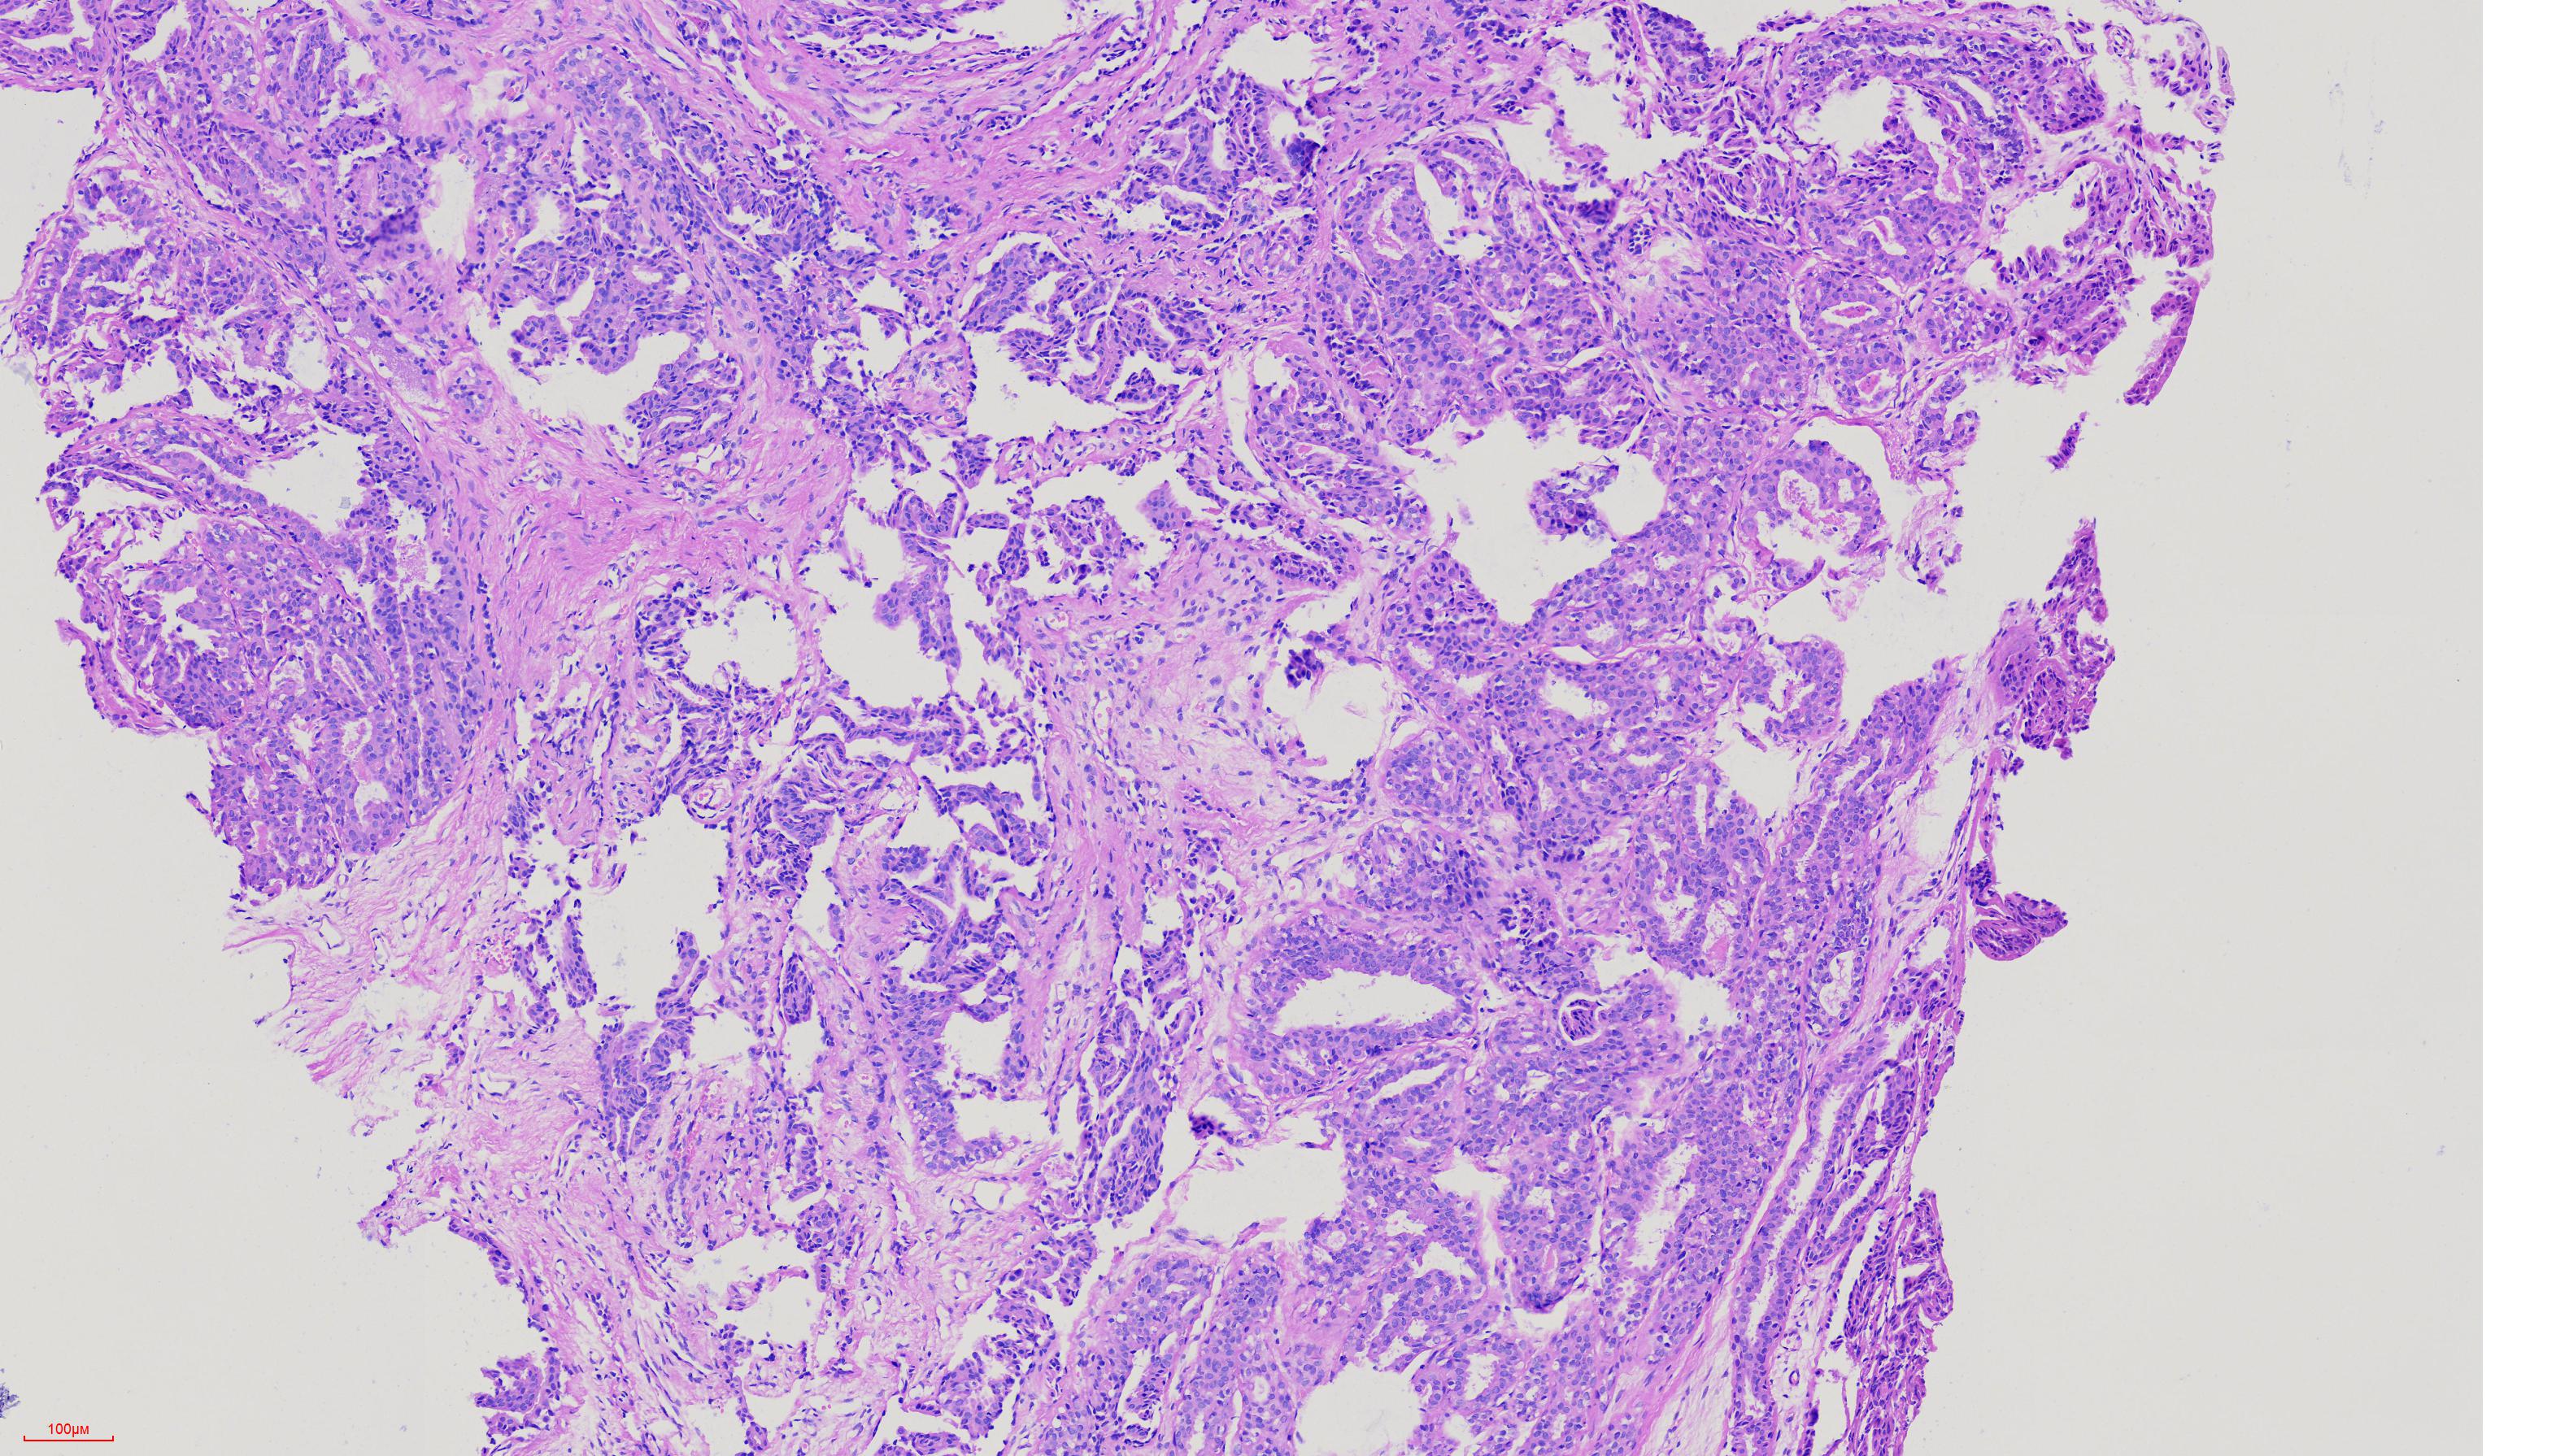

外阴肿物

性别

女

年龄

51岁

外阴肿物一年余

灰白色黄豆大组织

考虑为生乳头状汗腺瘤